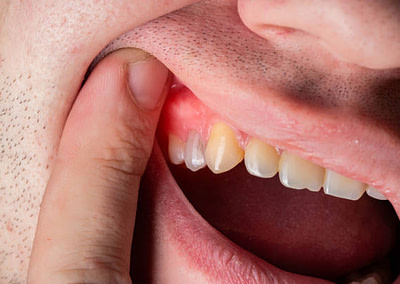

Gum Recession: Causes, Consequences, and Treatment Solutions

Gum recession is a common dental condition characterized by the gradual loss of gum tissue, exposing the roots of the teeth. While it can be a natural part of aging, gum recession can also result from various factors, leading to potential complications if left…

How to Manage Bleeding Gums

Bleeding gums can be a concerning and uncomfortable issue that many people face. If left unaddressed, it can lead to more serious dental problems. Fortunately, modern dentistry offers effective solutions like laser gum treatment to manage gum pain and bleeding. In…

Receding gums and root exposure and their management through soft tissue grafting

Gingival recession or receding gums are one of the consequences of periodontal bone loss. However, gingival recession can also be due to developmental reasons or even due to anatomical alterations resulting from orthodontic treatment. In any of these situations, when…